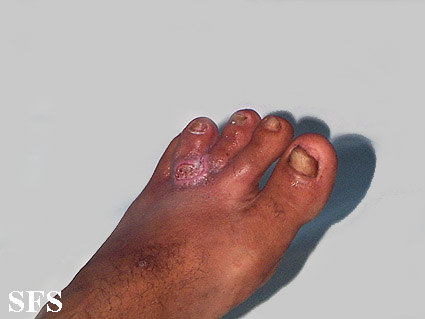

blastomycosis south american